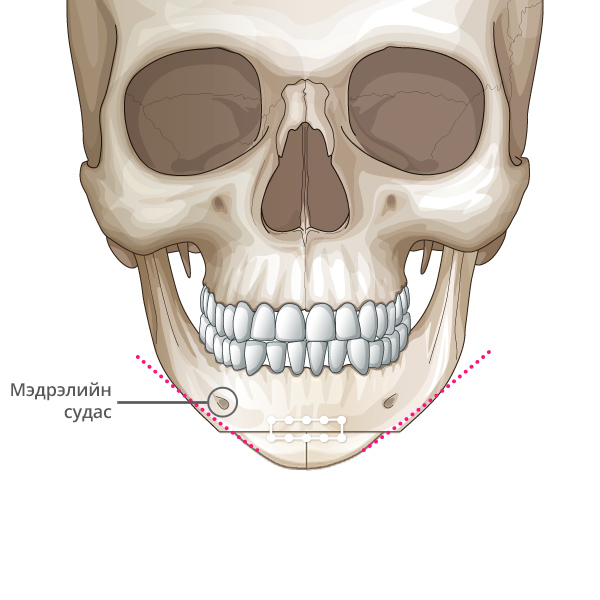

Мэдрэлийн судаснаас зайлсхийж, эрүүний төгсгөлд зүсэлт хийнэ.

Ясны гол хэсгээс тайралт хийж авна.

Зүсэлт хийгдсэн эрүүний хоёр талыг нийлүүлнэ.

Эрүүний ясыг нийлүүлж тогтоож өгнө.

Хоёр хажуу талд товойж харагдах ясны хэсгийг тайрна.